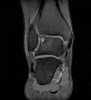

진단이 어려우면 MRI가 진단에 유용합니다.

MRI : 거골의 박리성 골연골염(Osteochondral lesion of talus)